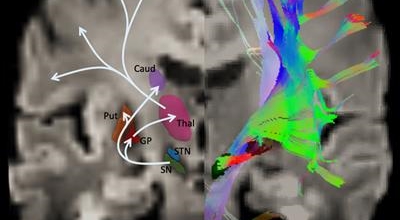

파킨슨병은 도파민 분비 신경 세포의 소실로 발생하는 질환으로 알려져 있는데요 도파민이란 뇌의 신경세포에서 만들어지는 물질로 세포와 세포 간의 신호를 전달하는데 이용되는 신경 전달 물질 중 한가지로 이 도파민이 감소함에 따라 파킨슨병이 걸린다고 하는데 이 도파민 세포가 떨어지는 이유는 아직 정확히 밝혀지지 않았다고 합니다.